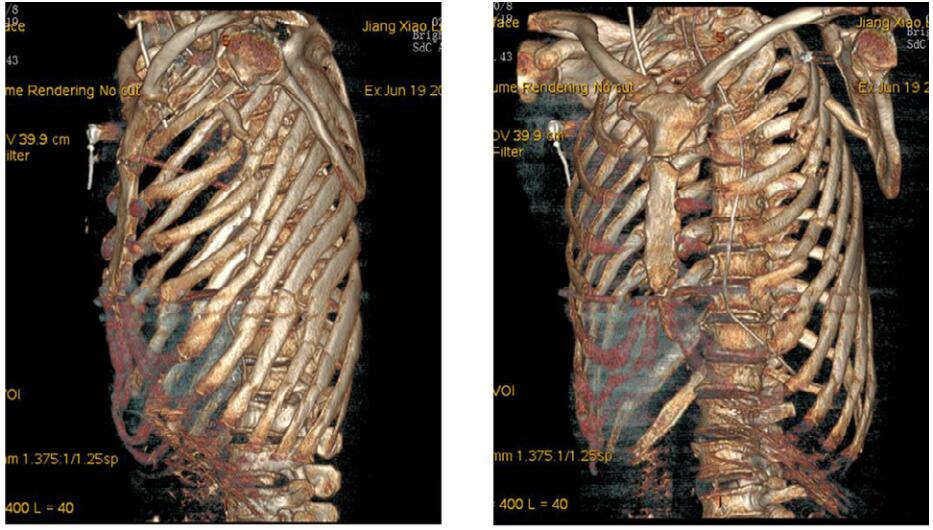

1 资料与方法患者,男性,54岁,因“重物砸伤致左侧肩部胸部疼痛、呼吸困难2 h”于2019年6月16日入院。患者2 h前在工地劳作时不慎被约20~30 kg重物砸伤,伤后即感左侧肩部胸部疼痛、呼吸困难,发病后无昏迷史、无恶心呕吐、无肢体抽搐、无大小便失禁。入院时查体:体温35.3 ℃,心率153次/min,呼吸27次/min,血压52/37 mmHg(1 mmHg=0.133 kPa),SpO2 77%(面罩吸氧5 L/min后上升至90%左右)。患者GCS评分15分,神志清楚,呼吸急促,左侧胸廓畸形,颈部、左前胸壁、左腋下、左上肢肿胀,左前胸壁可及皮下气肿,反常呼吸,四肢皮肤湿冷,左上肢活动障碍,桡动脉搏动较右上肢减弱,四肢末梢感觉无异常。急查床边超声示左侧胸腔积液,脾肾隐窝、腹腔未见明显积液。CT示颅内未见明显出血。左侧气胸伴左肺膨胀不全、挫伤,肺压缩约70%;左侧多发肋骨骨折,左侧颈部、胸部、侧胸部、背部皮下积气、血肿,见图 1。上下腹部未见明显外伤性改变。

| A、B:左侧气胸、左肺膨胀不全、左肺挫伤,C、D:左侧多发肋骨骨折、左侧胸背部皮下积气 图 1 患者急诊胸部CT |